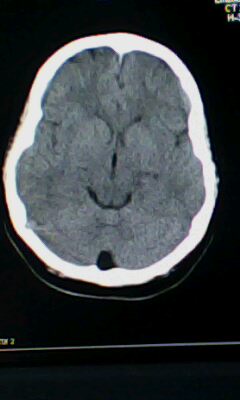

标题: CT25338:女 14岁 3岁时检查为脑积水 现在发育滞后 偶有尿失 [打印本页]

标题: CT25338:女 14岁 3岁时检查为脑积水 现在发育滞后 偶有尿失

颅脑ct轴位平扫颅内未见明确异常。

蛛网膜囊肿!

脑皮质增厚,发育异常!

左侧灰质异位

建议mri

颅脑ct轴位平扫颅内未见明确异常,建议mri。

左侧颞枕叶区密度异常?